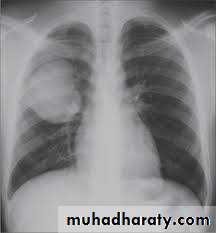

Pulmonary hydatid cyst